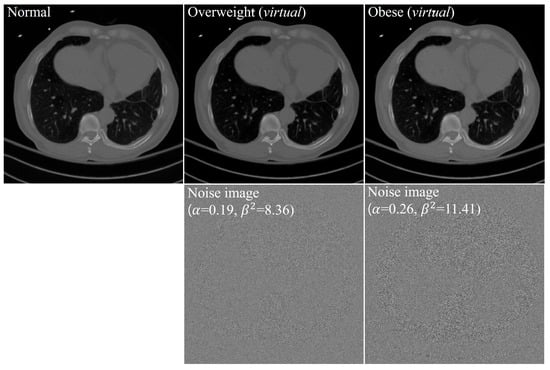

| Overweight | ||

|---|---|---|

| Patient 1 | 0.21 | 8.49 |

| Patient 2 | 0.16 | 8.35 |

| Patient 3 | 0.19 | 8.23 |

| Mean SD | 0.19 0.03 | 8.36 0.13 |

| Median | 0.19 | 8.35 |

| Minimum, maximum | (0.16, 0.21) | (8.23, 8.49) |

| 95% CI | (0.12, 0.25) | (8.03, 8.68) |

| Obese | ||

| Patient 1 | 0.25 | 11.36 |

| Patient 2 | 0.19 | 10.29 |

| Patient 3 | 0.27 | 10.42 |

| Patient 4 | 0.33 | 12.27 |

| Patient 5 | 0.27 | 10.67 |

| Patient 6 | 0.23 | 11.10 |

| Patient 7 | 0.36 | 14.04 |

| Patient 8 | 0.39 | 12.60 |

| Patient 9 | 0.33 | 12.42 |

| Patient 10 | 0.38 | 12.57 |

| Patient 11 | 0.16 | 11.31 |

| Patient 12 | 0.15 | 9.74 |

| Patient 13 | 0.17 | 10.22 |

| Patient 14 | 0.21 | 11.62 |

| Patient 15 | 0.17 | 10.59 |

| Mean SD | 0.26 0.08 | 11.41 1.17 |

| Median | 0.25 | 11.31 |

| minimum, maximum | (0.15, 0.39) | (9.74, 14.04) |

| 95% CI | (0.21, 0.30) | (10.77, 12.06) |